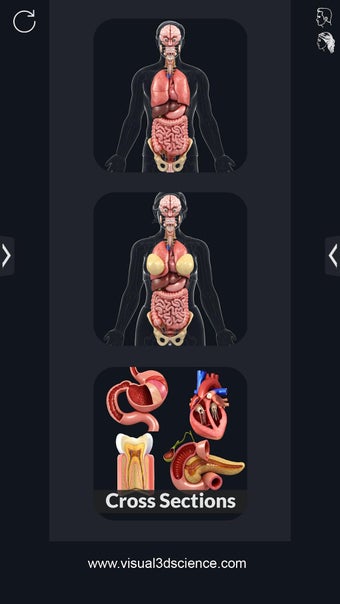

Dit is een zeer nuttige applicatie waarmee je het menselijk lichaam kunt verkennen.

Met deze applicatie kun je 360° draaien rond een zeer realistisch 3D-model van het menselijk lichaam. Je kunt in- en uitzoomen op elk deel om er beter naar te kijken.

Het is zeer eenvoudig te gebruiken en kan een zeer nuttige applicatie zijn voor iedereen die het menselijk lichaam moet bestuderen.